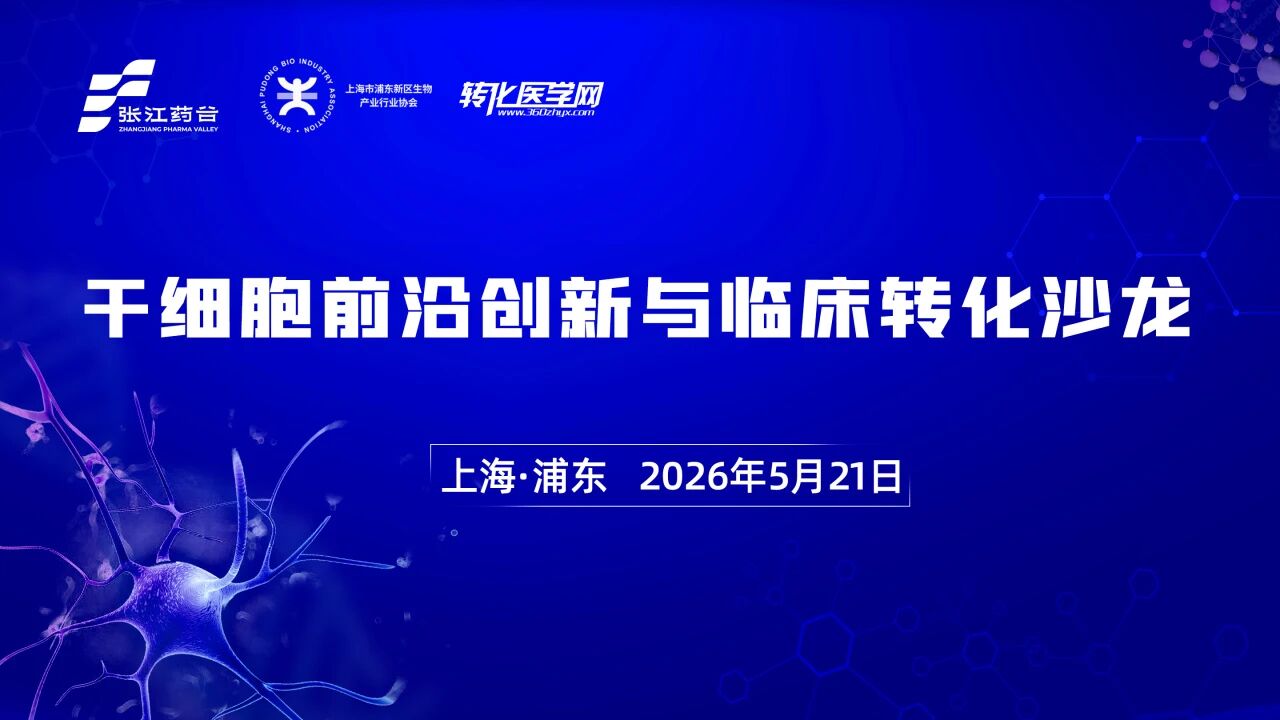

新政赋能,干细胞临床转化加速前行,5.21相约张江药谷,共话新机遇!